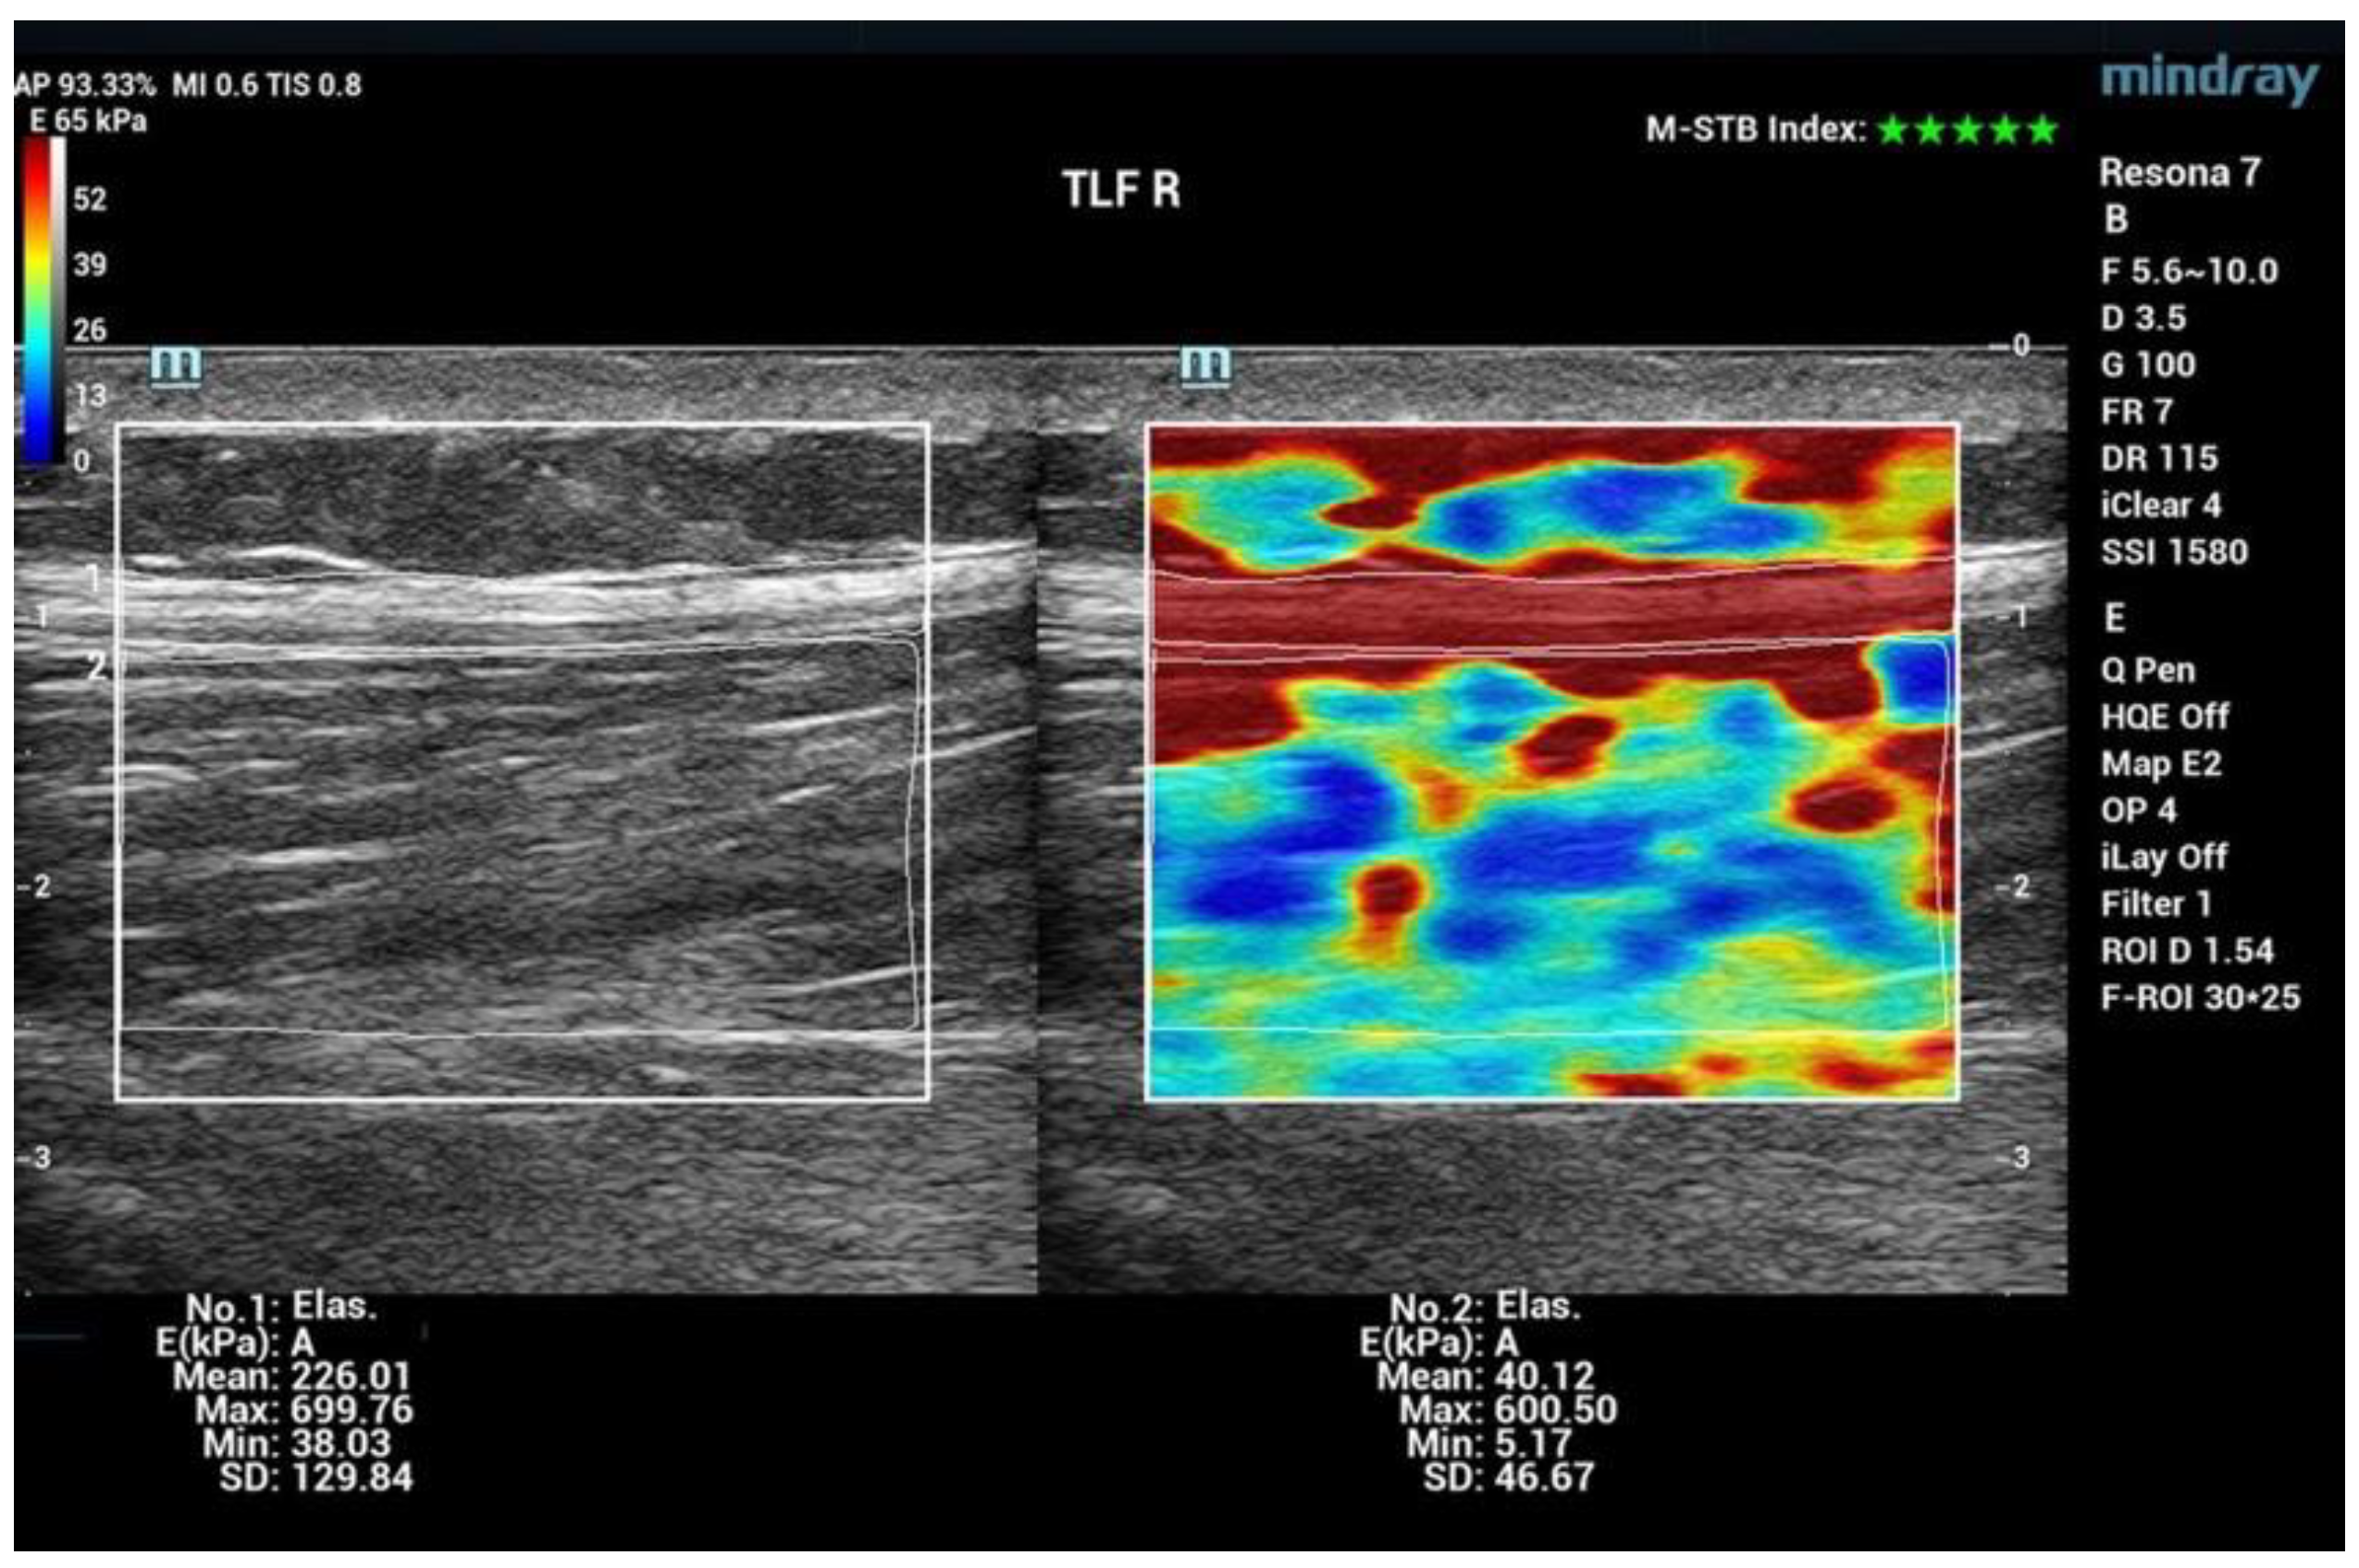

| 5 | Thoracolumbar fascia TLF L4/5 L | Line ilium upper margin A total of 2 cm paravertebral proc. spinous process | prone position |

| 6 | Thoracolumbar fascia TLF L4/5 R | Line ilium upper margin A total of 2 cm paravertebral spinous process | prone position |

| Thoracolumbar fascia | ||

| TLF Left | +15 | 0.039 |

| TLF Right | +17 | 0.003 |

| Thoracolumbar fascia | |||

| TLF R | +17 | +10 * | MR > CT |

| TLF L | +15 | +44 | CT > MR |

| Thoracolumbar fascia | |||||

| TLF L | −22.4 | 0.002 | −3.4 | 0.741 | −MR −CT |

| TLF R | −24 | 0.001 | -12 | 0.308 | −MR −CT |